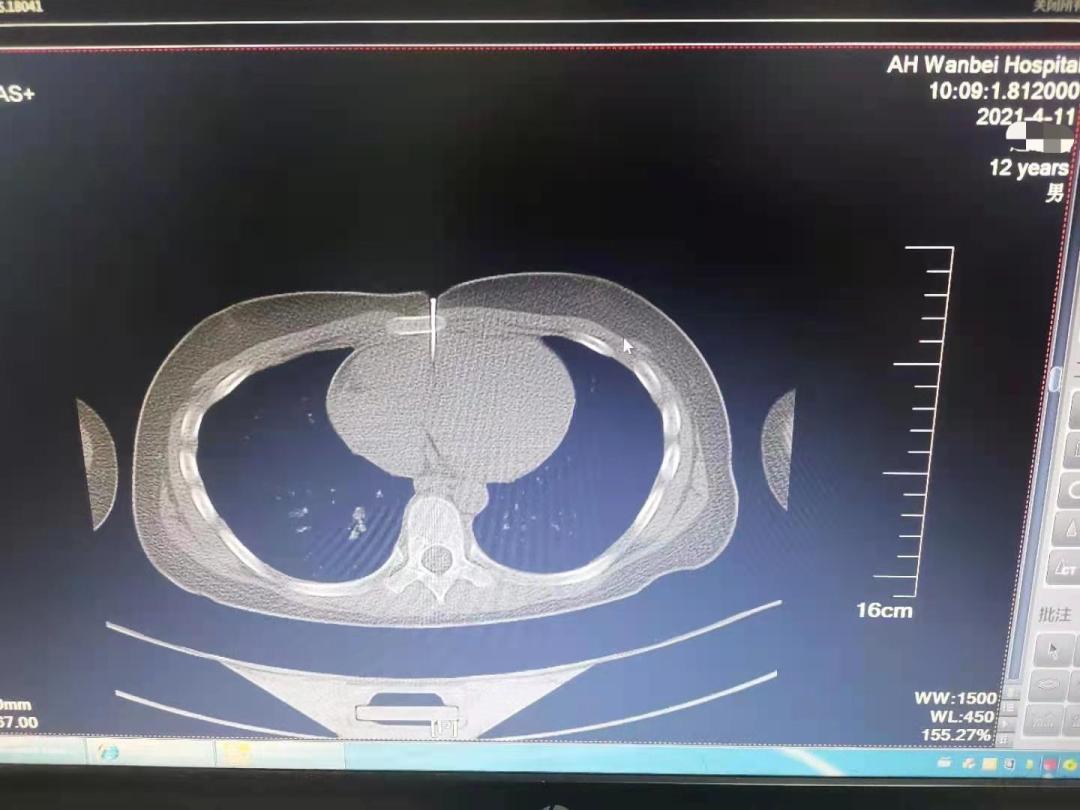

4月11日上午十点左右,宿州市的12岁男孩畅畅(化名)在家玩耍时,不慎被装修用的气钉枪击中胸部。长约4CM的钉子,穿透胸骨,直达心脏!

记者从安医大一附院获悉,该院高新院区紧急开辟绿色通道,心脏大血管外科团队、手术室、麻醉科迅速准备,经过2个小时的手术,钉子被顺利取出,破损的心脏也修补完好,畅畅转危为安。

据畅畅的家人介绍,当天上午家中正在装修,畅畅自己在旁边玩耍。听到叫声赶来才发现孩子误将气钉枪当玩具枪对着自己,触发了扳机,钉子已经穿透皮肤深入到体内。家人立刻将其送入当地医院,后直接转到安医大一附院急诊手术。

据安医大一附院心外科副主任医师龚文辉介绍,钉子根部都深入皮内,幸亏来的及时,否则心包填塞会导致心脏骤停。如果气钉打入的位置再高一点,打到主动脉,几乎就来不及医治了。